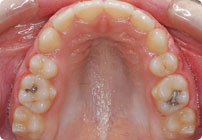

Caso: 11 años

Adolescente: Clase II

Mordida Cruzada Posterior

Sin extracción

Sin uso de expansores

6 alambres superiores

5 alambres inferiores

Sin uso de elásticos

Retenedores: Interior Fijo de TMA y Hawley en superior

Tiempo de tratamiento: 14 Visitas